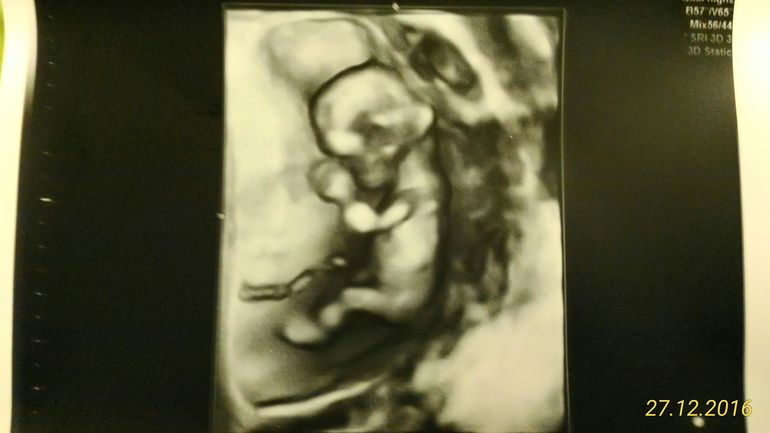

Зато на 21 недельке наш мужик все "хозяйство" показал

уже никак не ошибешься)

Вам еще мальчика кидали. Тоже торчок. Так что не думаю что это мальчик. По крайней мере у меня у всех 3 сыновей было как у 3 вот. .

Мне кажется больше похоже не девочку. У мальчиков бугорок повыше будет, а на фото прямо близко к попе. Кто знает... Но я за девочку.

Ну,не знаю.Не вижу я девочку.Мальчик.У моего сынули пятого так же было,такой же наклон.

вот УЗИ,смотрите как расположен бугорок